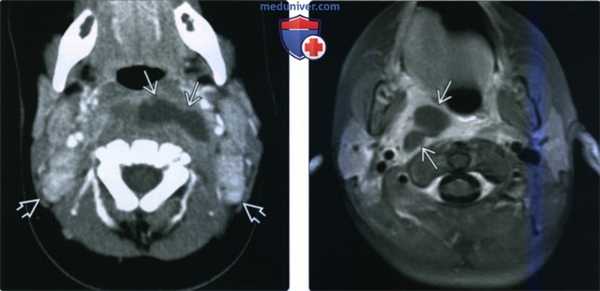

(Слева) КТ с КУ, аксиальная проекция. Ребенок пяти месяцев жизни. В заглоточном пространстве имеется скопление жидкости неправильной формы, распространяющееся в левую половину пространства. Вероятнее всего, гной прорвался из лимфоузла. Обратите внимание на наличие двусторонней шейной лимфаденопатии без признаков нагноения.

(Справа) МРТ Т1ВИ FS с КУ, аксиальная проекция. У ребенка имеется аллергия на йодсодержащий контраст. В правой половине заглоточного пространства четко визуализируется абсцесс. Окружающие ткани интенсивно накапливают контрастное вещество.

3. КТ при заглоточном абсцессе:

• КТ с КУ:

о Расширение ЗГП за счет скопления содержимого низкой: плотности + накопление контраста в стенках абсцесса:

- На ранних стадиях накопление контрастного вещества может быть незначительным

- Толстые стенки, в которых накапливается контрастное вещество, характерны для зрелого абсцесса

- Предпозвоночные мышцы тоже могут быть отечными

- Газ обнаруживается редко

4. МРТ при заглоточном абсцессе:

• У пациента с интоксикацией выполняется редко:

о Сужение просвета дыхательных путей, сложно контролировать состояние пациента

• Может быть полезным для того, чтобы отличить опасное пространство от скопления жидкости в ЗГП:

о Опасное пространство находится позади ЗГП, продолжается в средостение